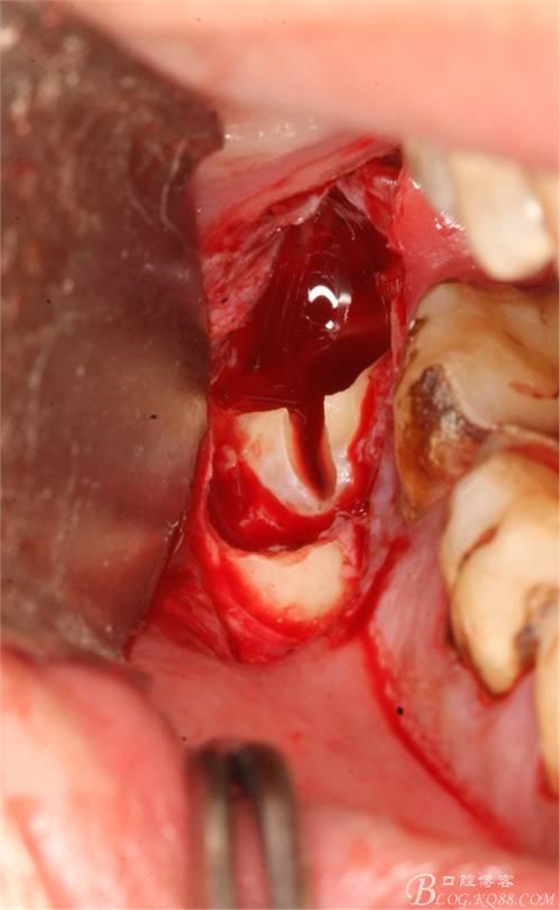

4.縱分牙根和牙冠

5.取出牙根